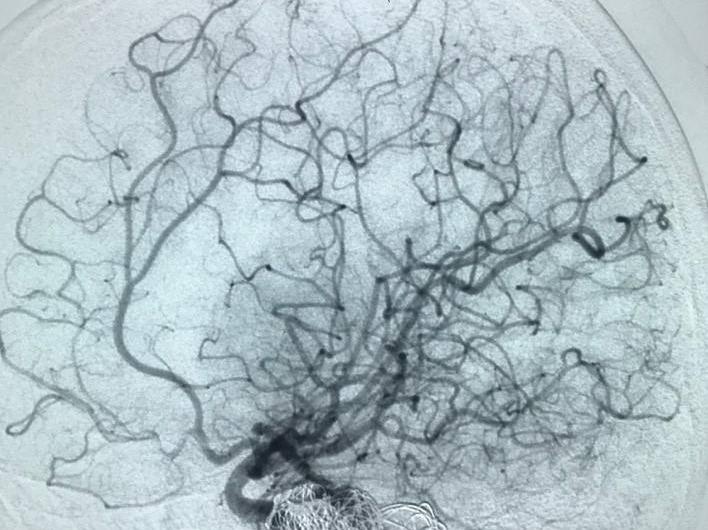

Bệnh nhân bị phình mạch máu não đã được điều trị thành công bằng phương pháp can thiệp nội mạch trong trạng thái hoàn toàn tỉnh táo.